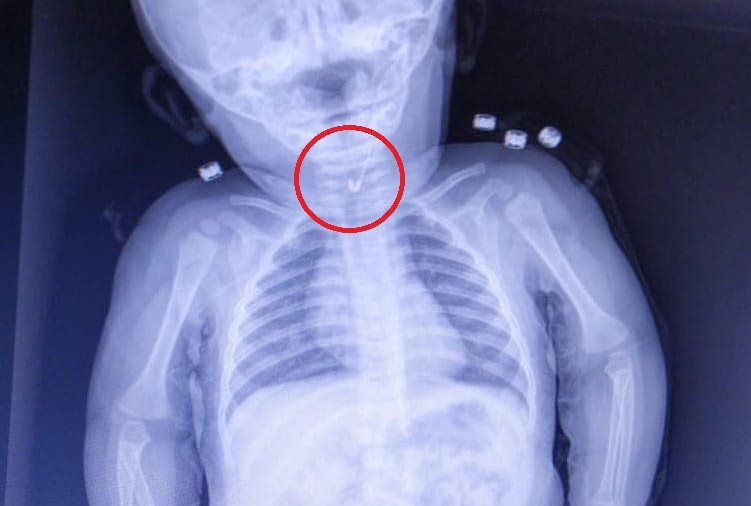

Tekirdağ’da 7 aylık bir bebek, yemek borusuna çengelli iğne kaçması sonucu Tekirdağ Devlet Hastanesine sevk edildi. 7 aylık erkek bebeğin yutup yemek borusuna takılan açık çengelli iğne Tekirdağ Devlet Hastanesi'nde yapılan girişim ile başarıyla alındı. Gastroenterolojik Cerrahi Uzmanı Dr. İhsan Gündüz ile Anestezi Uzmanı Dr. İbrahim Çetin'in yaptığı operasyon sonucu bebek sağlığına kavuştu.